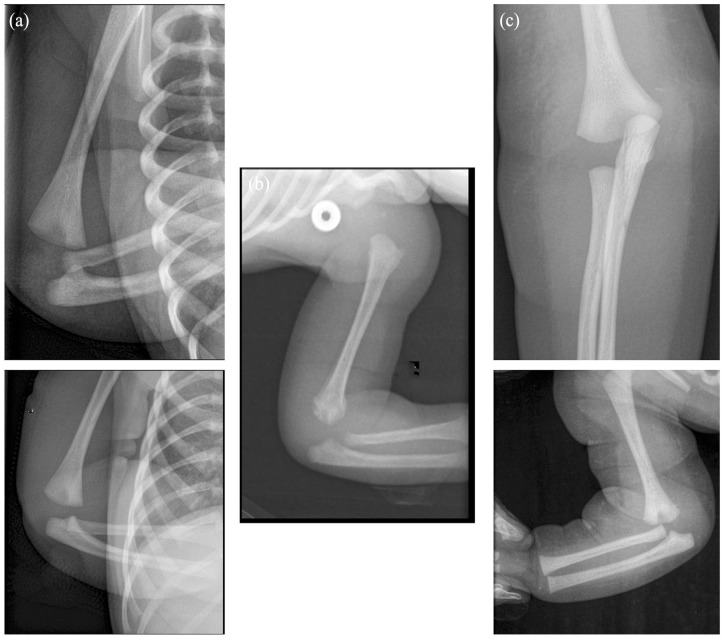

Background: The newborn transphyseal fracture of the distal humerus is frequently misdiagnosed with an elbow dislocation due to the absence of the lateral condyle ossification node. No consensus has been reported either for the diagnosis or the management of these rare fractures. This study aimed to analyze a series of newborns with transphyseal distal humerus fractures.

Methods: All consecutive infants treated between 2005 and 2020 for a transphyseal fracture of the distal humerus before the age of 6 months were retrospectively included. All radiological examinations were analyzed (X-ray, ultrasound, and magnetic resonance imaging (MRI)) as well as the therapeutic management (orthopedic or surgical treatment). The patients were seen at outpatient clinic visits with a minimum of 2-year follow-up.

Results: Nine newborns were treated. The main cause was an obstetrical traumatism (n = 8). The diagnosis was made on physical examination and addressed by obstetric departments with standard biplanar radiographs in four cases. The fracture was suspected on physical examination in the remaining five cases and confirmed by complementary imaging (ultrasound (2), MRI (1), and both (3)). A total of six patients were treated conservatively and three surgically with an open reduction. At a mean follow-up of 79 months, two complications occurred: one axillary abscess due to the cast and one cubitus varus deformity. All children had a full functional recovery.